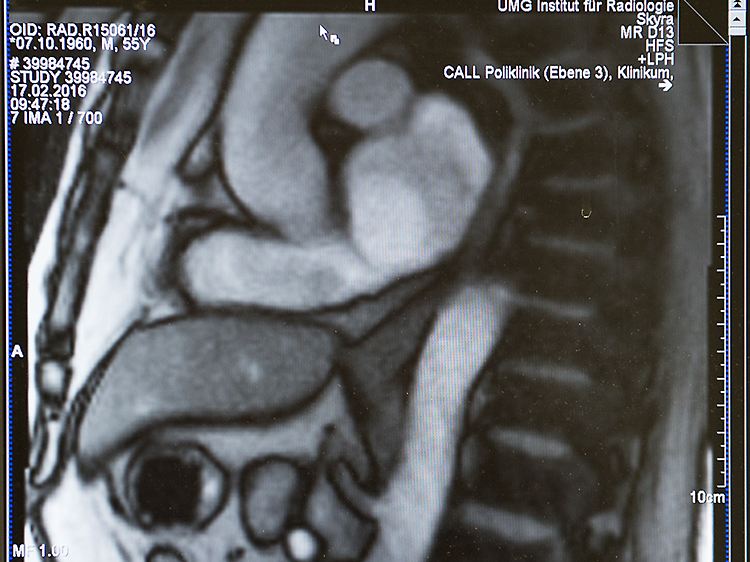

Das Standbild aus dem Echtzeit-MRT zeigt die Speiseröhre und den Übergang zum Magen.

Ärzte haben eine neue Methode entwickelt, um den Vorgang des Schluckens mit einem bildgebenden Verfahren zu beobachten. Mit Hilfe der Magnetresonanz-Tomografie (MRT) ist es dem Team aus Medizinern der Universitätsmedizin Göttingen (UMG) und Forschern des Max-Planck-Instituts (MPI) für biophysikalische Chemie Göttingen erstmals gelungen, mit 25 Bildern pro Sekunde das Schlucken in Echtzeit zu dokumentieren.

Mit den Bildern des Echtzeit-MRT können die Mediziner den Schluckvorgang vom Mundraum durch die Speiseröhre bis zum Mageneingang verfolgen. Auch der sogenannte Reflux, der entscheidende Akt für Sodbrennen, lässt sich unmittelbar beobachten: Um den Eintritt von Magensäure in die Speiseröhre auszulösen, reicht eine einfache Pressung auf den Bauch des Patienten.